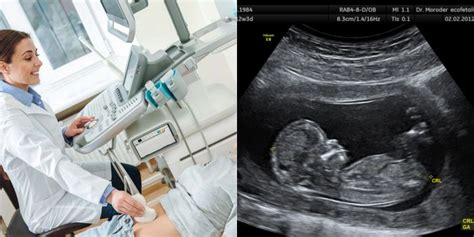

- Vaisiaus tyrimas ultragarsu: Šis tyrimas yra labiausiai paplitęs prenatalinės diagnostikos metodas, leidžiantis nustatyti daugumą struktūrinių defektų ir įtarti kai kurias vaisiaus ligas, kurių tikslinimui naudojami kiti diagnostiniai metodai. Pirmąjį nėštumo trimestrą (11-14 nėštumo savaitę), įvertinus vaisiaus dydį ir anatomiją, vertinama Dauno ligos rizika pagal vaisiaus požymius (sprando srities peršviečiamumą (SSP), nosies kauliuką ir kt.). Tyrimas ultragarsu nėra tikslus - net ir patyrę echoskopuotojai gali nepastebėti sutrikimų, matavimai gali būti netikslūs.

Pirmasis vaisiaus tyrimas ultragarsu reikšmingas ne tik kaip galimybė įvertinti vystymosi procesus, bet ir kaip svarbi tėvų pažintis su vaiku. Pastebima, kad tuo momentu, kai monitoriaus ekrane tėvai išvysta vaiką, užsimezga arba dar labiau sustiprėja svarbus tarpusavio ryšys. Taip pat geriau suvokiama juos aplankiusi naujiena.